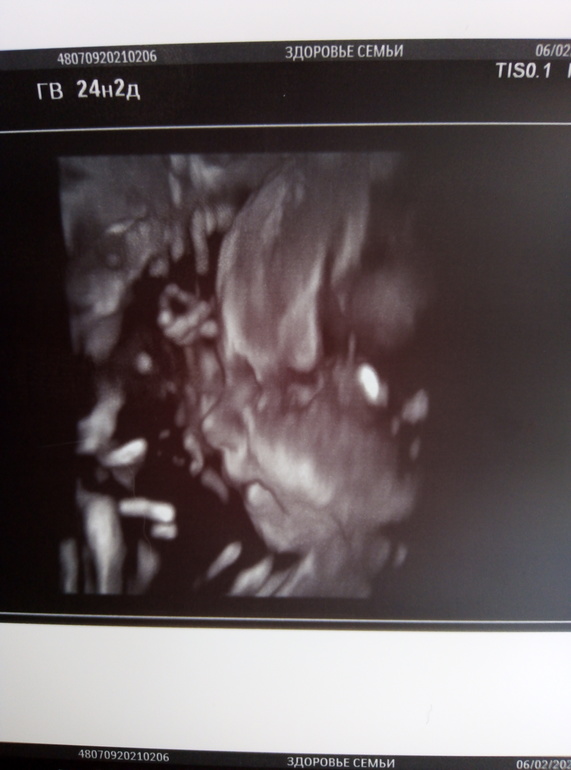

25 НЕДЕЛЬКА фотопуз + УЗИ❤️

Стартовала 25 неделя, как же быстро летит время, сгонял на доплер, заодно посмотрели дочу в 3д, ну и всё остальное быстро глянули, всё хорошо тьфу тьфу, волосы говорит длинные уже у вашей принцессы, я аж удивилась, показала мне прям волосы на голове ёжик такой прям, а фото в 3д боже такой гномик шладкий и тут я поняла что мы вылитый папа))))